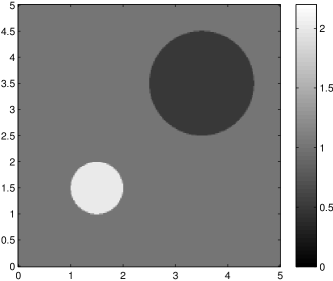

The data (see Figures 1 and 2) was generated in the diffusion model (1.2) using self-written (linear-basis) finite element code in MATLAB. For both examples, we took and used a uniform boundary condition . The simulated data were generated on a -grid and then down-sampled (by averaging) to to avoid inverse crime. After that, Gaussian noise with different intensities (standard deviations of and of the average signal value ) was added to the data.

Reconstruction results and error profiles at different noise levels can be seen in Figures 3 and 4. In both examples, the noise-free reconstructions are very accurate and contain mostly smoothing error. In the low-noise reconstructions, due to the fact that more regularization is necessary, some of the parameter variation is underestimated. In the high-noise examples, most detail in is lost since a lot of regularization is required to get reasonable results. The fine detail in can, however, still be recovered very accurately in both examples.